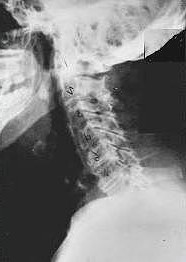

Phase Two Subluxation Degeneration

Phase two subluxation degeneration is normally seen in subluxations that have been present between 20 and 40 years.  This phase has some of the same characteristics of the previous phase including a loss of normal curvature and position as well as an alteration in segmental motion.  In addition, spines with Phase Two Subluxation Degeneration many times show a reduction in the patient’s range of motion in that area.  X-rays of a phase two begin to show calcium changes or buildup at certain levels of the spine.  These changes are sometimes called by many names including spurs and arthritis.  Disc spaces between the affected vertebrae are noticeably narrower and may appear to be flattening out.  Although most people with Phase Two Subluxation Degeneration may not exhibit any symptoms, some may start to feel stiff or achy.  Chiropractic reconstructive care for patients in phase two ranges from 1.5 years to 2.5 years.  Again, if Phase Two Subluxation Degeneration is left uncorrected it slowly advances to the next phase.